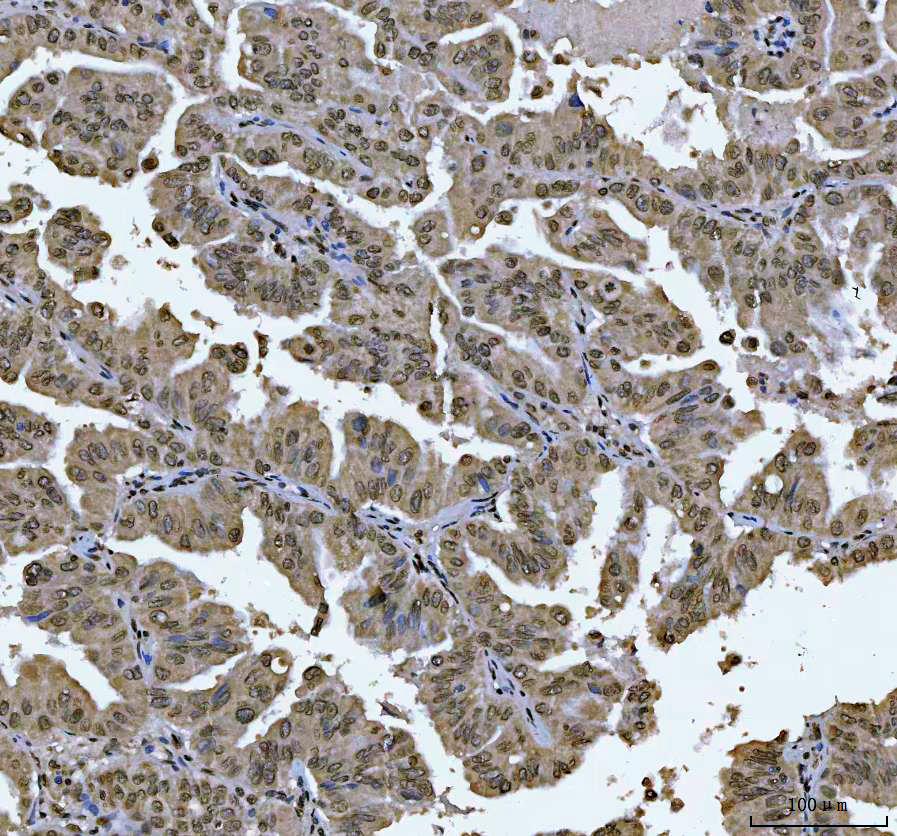

IHC analysis of ZEB1 using anti-ZEB1 antibody (M00548-2).

ZEB1 was detected in a paraffin-embedded section of human Colorectal adenocarcinoma tissue. Biotinylated goat anti-mouse IgG was used as secondary antibody. The tissue section was incubated with mouse anti-ZEB1 Antibody (M00548-2) at a dilution of 1:200 and developed using Strepavidin-Biotin-Complex (SABC) (Catalog # SA1021) with DAB (Catalog # AR1027) as the chromogen.